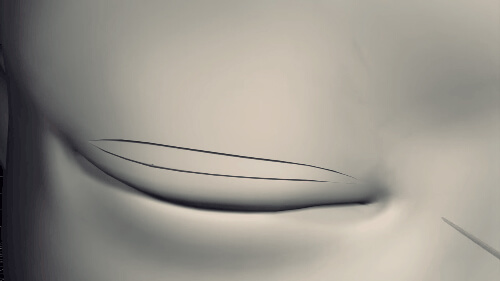

Đầu tiên, các bác sĩ sẽ đo và vẽ viền mi mắt cho bạn rồi dùng dao, kéo rạch liên tục theo đường viền vừa vẽ. Tiếp theo, bác sĩ cắt bỏ một phần mô ở mi mắt…

… rồi tạo sự liên kết bằng cách khâu cân cơ nâng mi với da.